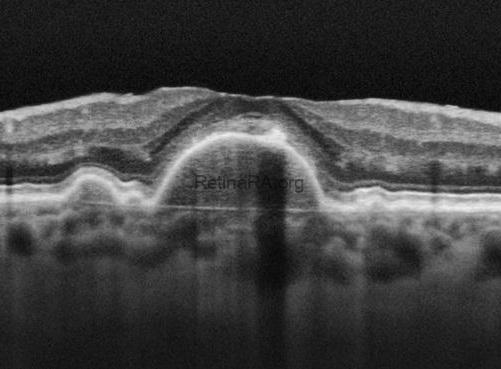

Drusen may grow and coalesce to form drusenoid pigment epithelial detachment (PED). Although there is no definitively accepted value, drusen larger than 350 microns have been accepted as drusenoid PED in some clinical studies. On color fundus photography, the Drusenoid PED appears as a large yellow, raised area above the surface. RPE proliferation may accompany. OCT provides a definitive diagnosis of drusenoid PED. Note that hyperreflectivity of drusen and drusenoid PED are same. RPE proliferation, seen as a gray-brown area within the drusenoid PED on color photography, is observed as a hyperreflective formation at the level of the RPE causing shadowing underneath on OCT.

OCT of drusenoid PED